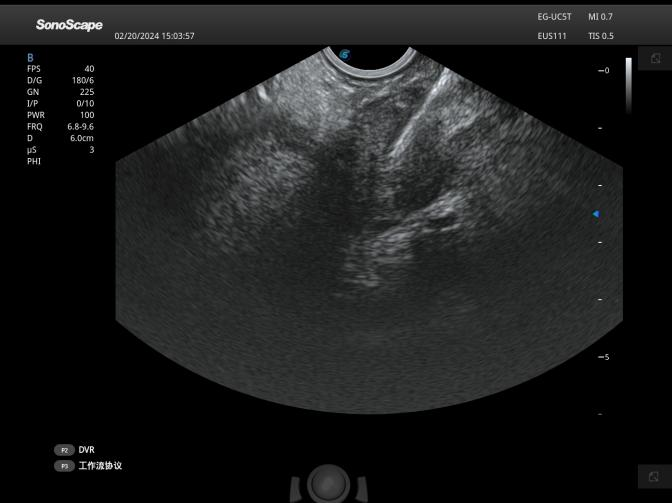

中年男性患者,腹痛3月,多次影像学检查提示胰腺病变,但具体良恶性质一直未能得到明确。由于胰腺位置深,经皮穿刺很多情况下无法获取胰腺肿瘤标本,而超声内镜技术可在胃或十二指肠内以最近的距离对胰腺进行扫查,并进行穿刺活检。经白云医院消化内科会诊后,及时安排实施超声内镜引导下细针穿刺术(EUS-FNA),医院消化内科刘朋副主任用精湛医术护佑生命健康,手术顺利完成,术中在超声内镜扫查下已基本诊断为恶性肿瘤,术后穿刺组织条在病理科医师耐心、专业的阅片后确诊为胰腺癌,病变的良恶性终于明确,患者也即将进行肿瘤专科治疗。

超声引导下穿刺

“4E”技术是指消化内镜难度较大的4类手术,包括:EUS(超声内镜)、ESD(内镜粘膜下剥离术)、EVL(内镜下食管静脉曲张套扎术)、ERCP(经内镜逆行胰胆管造影术) 。超声内镜(EUS)是将内镜和超声相结合的消化道检查技术,将微型高频超声探头安置在内镜顶端,当内镜插入体腔后,在内镜直接观察消化道黏膜病变的同时,可利用内镜下的超声行实时扫描,可以获得胃肠道的层次结构的组织学特征及周围邻近脏器的超声图像。超声内镜引导下细针穿刺(EUS-FNA)就是在超声内镜引导下运用一根纤细的活检针经过内镜活检孔道对相应病变进行抽吸活检,通过活检,可以获得病灶的细胞、组织学诊断,从而明确病变性质。